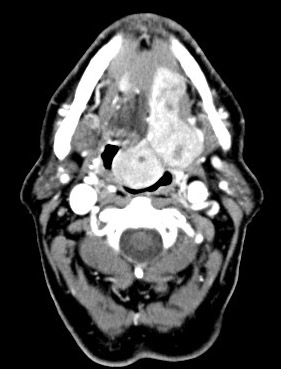

The patient was a 76 year-old man. He was referred from an outside hospital because of a large mass at the base of his tongue obstructing the airway and also with complain of difficulties in swallowing. A well circumscribed pedunculated mass was demonstrated by CT scan. A fine needle aspiration was performed and the mass was excised in our institute.